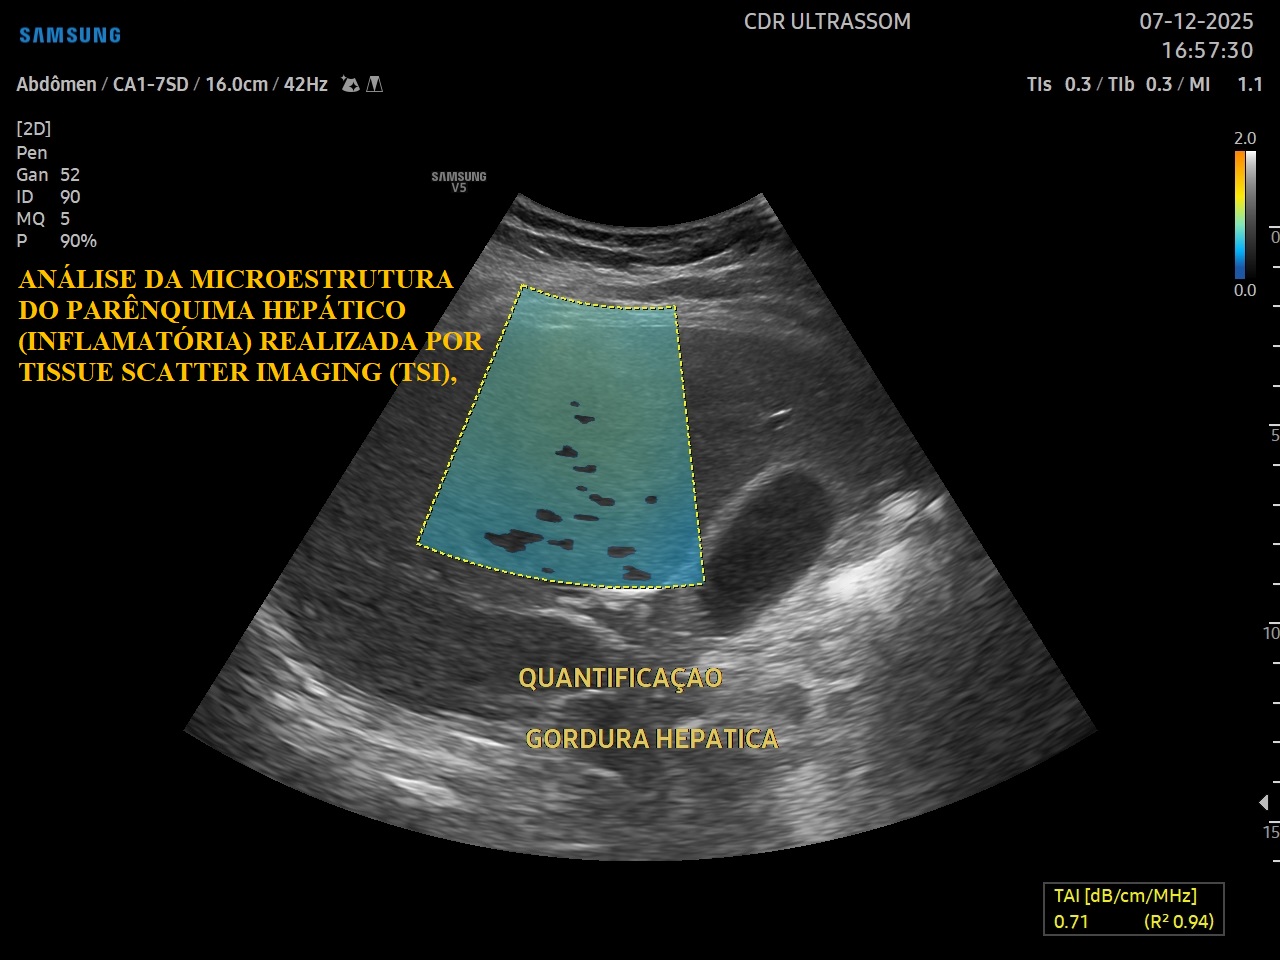

A elastografia e a quantificação da gordura hepática por ultrassonografia multiparamétrica representam uma tecnologia moderna e não invasiva para avaliação da saúde do fígado. Por meio de técnicas avançadas de ultrassom, é possível analisar de forma objetiva tanto a rigidez do tecido hepático, relacionada à fibrose, quanto o teor de gordura presente no órgão, com alta precisão diagnóstica.

Essa tecnologia vai além do ultrassom convencional ao utilizar parâmetros quantitativos validados cientificamente, com excelente correlação com métodos de referência como a ressonância magnética. Dessa forma, permite diagnóstico precoce, estratificação de risco e acompanhamento evolutivo das doenças hepáticas, qualificando a avaliação clínica e auxiliando na tomada de decisões médicas baseadas em evidência.

- Coeficiente de Atenuação (CA)

- Retroespalhamento (BSC)

- Fração de Gordura por Ultrassom (USFF)

- Velocidade do Som (SoS)

Permite detectar e quantificar o acúmulo de gordura hepática de forma precisa, inclusive em fases iniciais da doença.